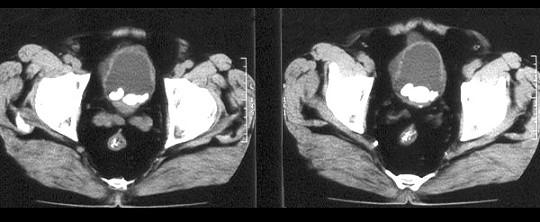

问题 男,58岁。大量无痛肉眼血尿伴血凝块1天,排尿困难1天。检查:血压120/75mmHg,脉搏82次/分,耻骨上及脐下压痛,叩诊浊音。 B超提示右肾占位性病变,为明确肿块性质,应首选 ( )

选项 A、CT B、腹膜后充气造影 C、逆行肾盂造影 D、KUB E、IVU

答案 E